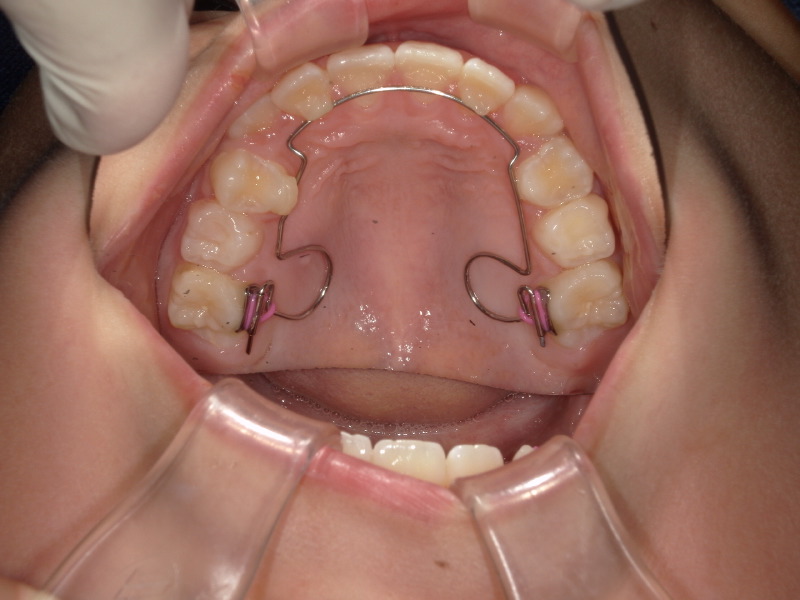

bwsの装着

マウスピースとアクティビティーをしている中で併用する装置があります。

舌のお手伝いをしてくれます。

またマウスピースも一緒に使うことができるのでとてもいい装置です。

初めにつけた時は上顎に少しの違和感は感じますがみんなすぐに慣れてくれます。

歯が少しずつアーチの方によっています。

ここまでくれば綺麗にアーチの中に入れそうなので装置も外しています。

長く使わないことも併用装置のメリットです。